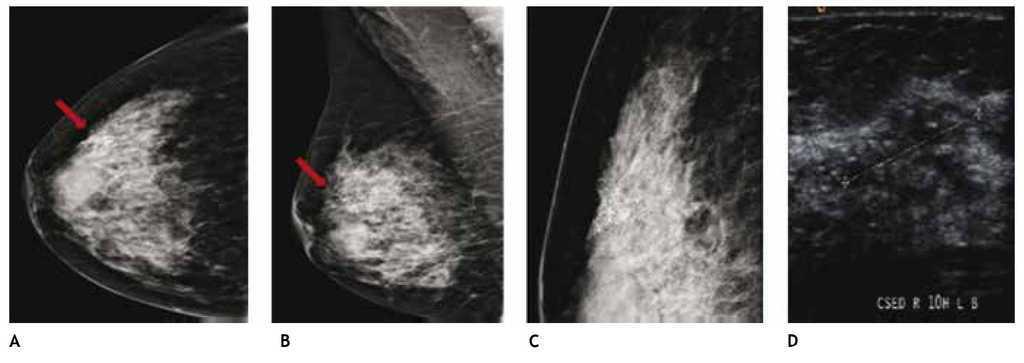

El carcinoma ductal in situ (CDIS), se presenta comúnmente con microcalcificaciones agrupadas en el 62% a 72%9 (figs. 2A-D) y gracias a esta tecnología su frecuencia relativa ha aumentado en los últimos años, así como la detección de lesiones precursoras o limítrofes como la hiperplasia ductal con atipia (fig. 3).

Figura 2 A), B) y C) Paciente de 48 años, asintomática, calcificaciones agrupadas polimorfas con distribución segmentaria CSED (flechas). D) ultrasonido, tumoración mixta, BIRADS 5: cáncer ductal in situ de alto grado.

El CLI es de difícil diagnóstico en la mastografía, ya que su presentación más frecuente es como una tumoración con densidad similar al tejido mamario, generalmente sin microcalcificaciones o distorsión de la arquitectura en el 10% a 34%, seguido de asimetría en la densidad; otra de sus características relevantes y que lo hacen más agresivo en relación al cDi, es la mayor frecuencia de multicentricidad y bilateralidad, por lo que el ultrasonido juega un papel importante en el diagnóstico de esta variedad histológica (figs. 6A-D).

Figura 6 A) y B) Paciente asintomática de 44 años de edad. Tejido heterogéneamente denso, por lo que se recomienda ultrasonido. C) Quiste simple (flecha corta) y tumoración hipoecoica e irregular (flecha larga). D) Tumoración no identificada en la magnificación, BIRADS 4 C: cáncer lobulillar infiltrante.